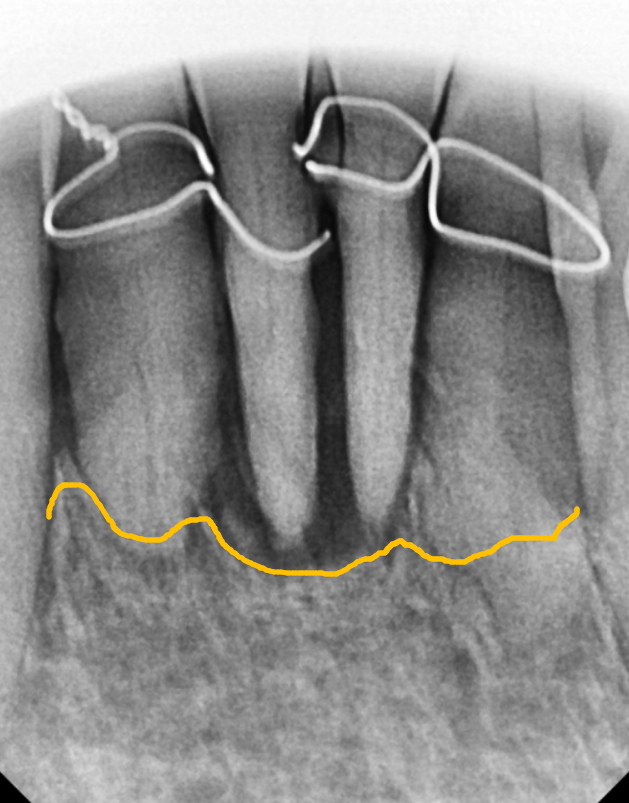

주변 잇몸뼈가 광범위하게 녹아내려

결국, 앞니 4개를 모두 발치하고

임플란트를 진행했습니다.

오랜 염증으로 잇몸뼈가 많이 내려가 있는 상태라,

일반적인 보철물을 올리면

치아가 비정상적으로 길어 보여

인상이 어색해질 우려가 컸는데요~